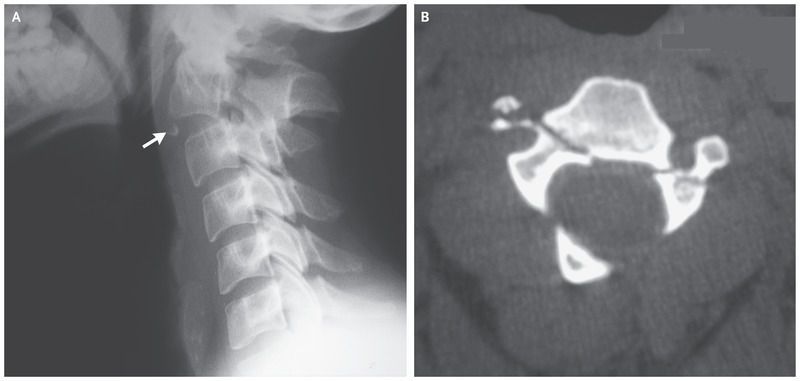

A 25-year-old man presented to the emergency department with severe neck pain after he was involved in a high-speed collision between two vehicles. He had full strength in his arms and legs, normal sensation to light touch and pinprick, and no sphincter disorders. A lateral radiograph (Panel A) showed disruption of the intervertebral disk between the C2 and C3 vertebrae, posterior angulation of the C2 vertebra fragment, fracture of the left pedicle of the axis, and a small inferior anterior fragment (arrow). An axial computed tomographic scan (Panel B) confirmed that the right and left pedicles of the C2 vertebra were fractured. Traumatic spondylolisthesis of the axis, also known as a hangman’s fracture, is caused by hyperextension of the neck. These fractures are classified according to the degree of anteroposterior deviation, presence of disruption of the posterior longitudinal ligament, position of the fracture line, and presence of a facet-joint dislocation. Stable fractures with minimal displacement may be managed conservatively with external immobilization, but unstable fractures, as in this case, require surgical stabilization. The patient underwent anterior fusion of the C2 and C3 vertebrae, and at follow-up 4 years later, he had no neurologic deficits and was free from pain.